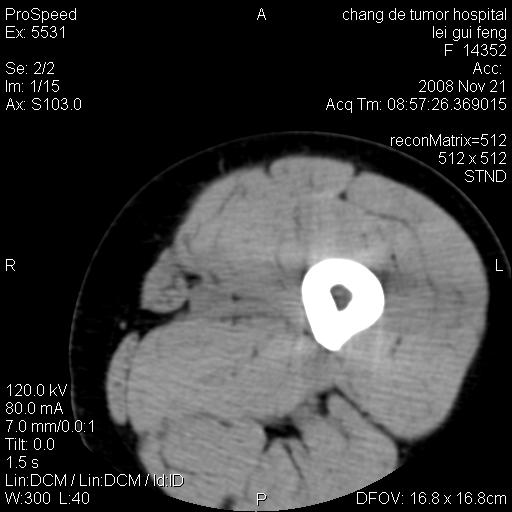

标题: CT16807:女 41 无不适 [打印本页]

标题: CT16807:女 41 无不适

双是软组织肿瘤,病灶内多发钙化,另可见多量脂肪密度影,考虑畸胎瘤,血管瘤,不除外其他